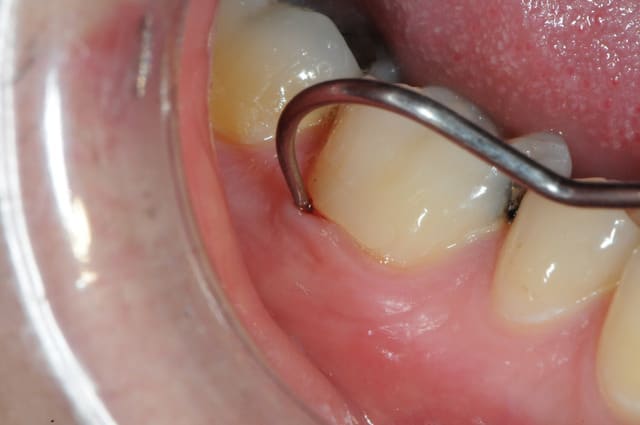

je fais une radio, et là.! voici ce qu'on trouve; une jolie cavité dans laquelle la sonde pénètre bien facilement.

je vais faire un lambeau muco-périosté, sécher et isoler au mieux avant de reconstituer.

mais avec quoi ? amalgame, composite, onlay, ..????

comment va se comporter la gencive en contacte avec cette restauration ???

1- c'est ma vue qui me joue des tours ou on peut voir un compo cervical en juxta gingival?

2- si c'est le cas, l'accès à la cavité me paraît tout trouvé

3- avec un bon écarteur de gencive on doit pouvoir commencer à cureter, manuellement d'abord puis à la fraise H1SM céramique de Komet parfaitement atraumatique et respectant la dentine dure, saine ou réactionnelle